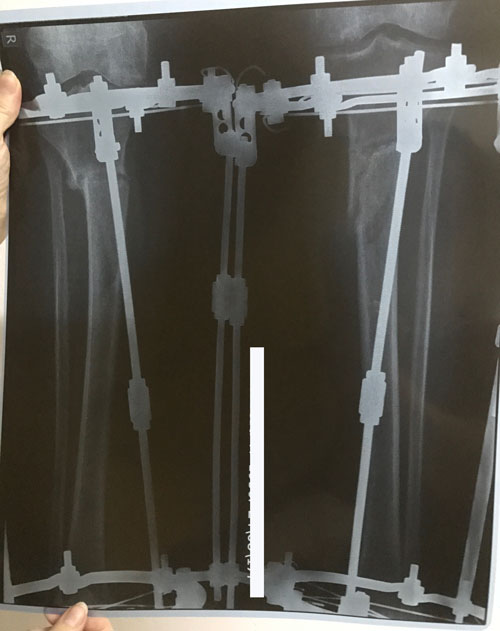

В процессе круток

Рентген и ото ножек в 60 дней.

Срастаетесь, как молодые девчонки

Спасибо за дисциплинированность! Всегда высылаете всё во время.